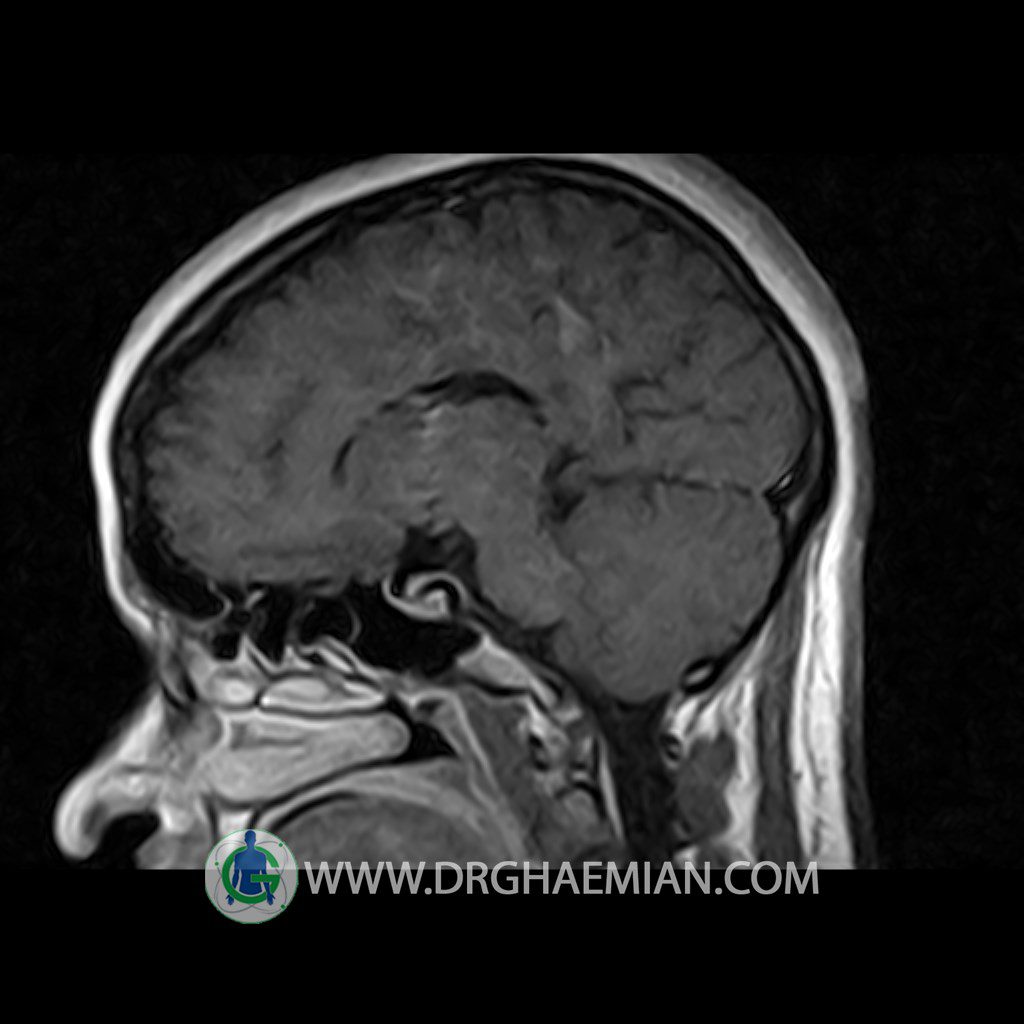

ام آر آی هیپوفیز یک روش تصویر برداری است که از غده هیپوفیز (غده ایی کوچک در مغز که هرومون ها و دیگر غدد بدن را کنترل می کند) و ناحیه های پیرامونش در مغز تصاویری ایجاد می کند. در این کیس سلای نسبتا خالی در ناحیه هیپوفیز بیمار مشاهده می شود.

HYPOPHYSIS MRI

(with and without contrast)

Technique: Axial , coronal T1 , Axial , coronal , sagittal T2 , Axial, coronal T1 post Gd & 64 dynamic thin coronal slices.

REPORT :

The pituitary tissue shows normal , position, shape , size and homogeneous signal intensity both before and after contrast administration .

Anterior and posterior pituitary gland were normal .

It contains no circumscribed hypointense or hyperintense areas .

The infundibulum is centered and of normal size .

The optic chiasm and suprasellar spaces appear normal .

The cavernous sinus and imaged portions of the internal carotid artery and carotid siphon are unremarkable .

Evaluable portions of the neurocranium show no abnormalities .

The sphenoid sinus is clear and pneumatized .

Imaging of the hypothalamus after contrast medium administration was normal.

– Extension of suprasella cistern to sella with thin pituitary gland in floor of sella ( partial empty sella )

is seen